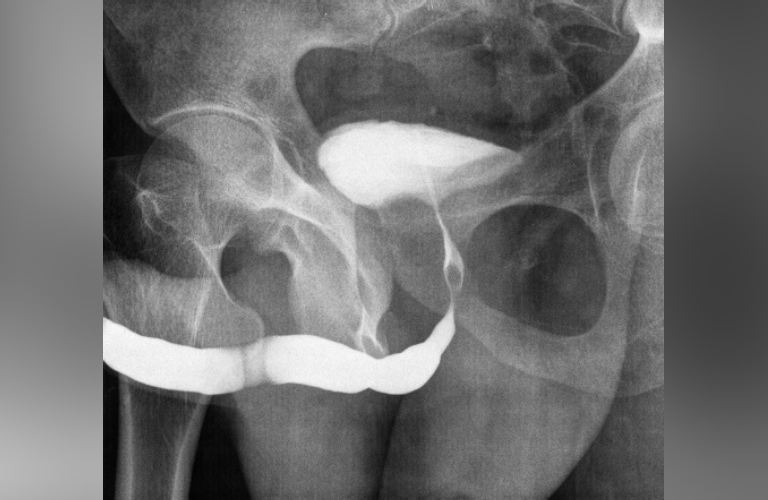

ESWL (Shock-Wave Lithotripsy)

A non-invasive procedure that uses focused shock waves to break kidney stones into tiny fragments, allowing natural passage without cuts, stitches, or long recovery.